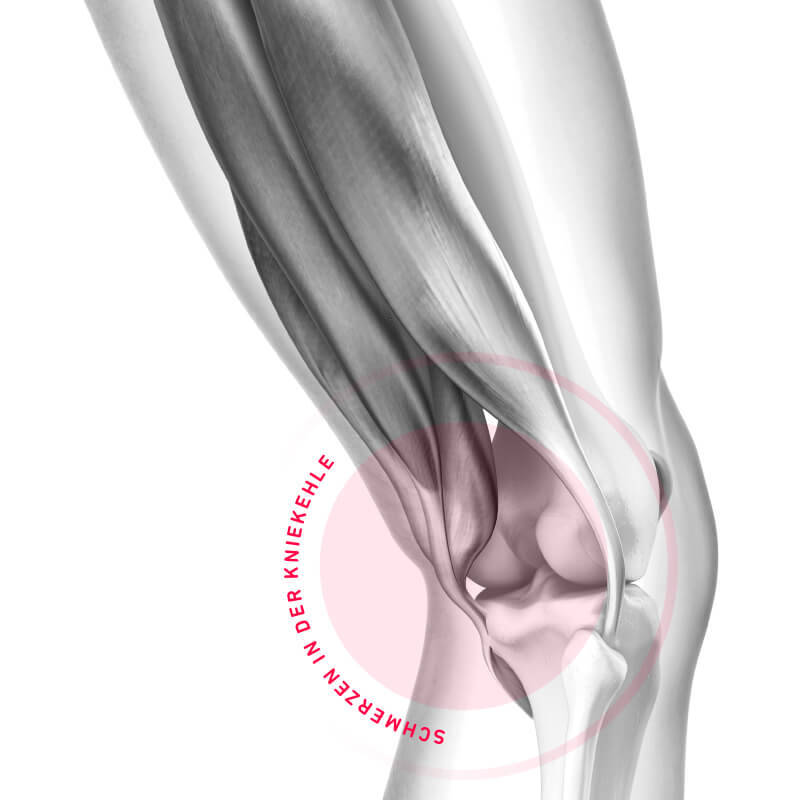

Schmerzen in der Kniekehle

Schmerzen im hinteren Teil des Knies sind zunächst oftmals rätselhaft. Was dahinter stecken und Du dagegen tun kannst, haben wir hier zusammengefasst.